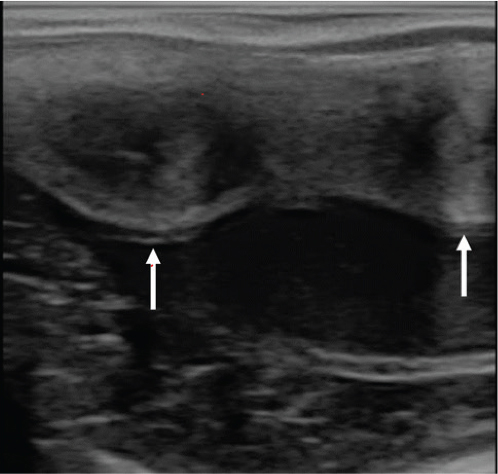

On presentation, mare was bright and alert. Her external genitalia had upright vulvar orientation, ~ 80% vulvar opening was below pelvic brim with appropriate vulvar and vulvo-vaginal seals. Transrectal palpation revealed symmetrical uterine horns and ovaries of adequate size, shape, tone, and texture for a cyclic, maiden, draft mare. Transrectal ultrasonography revealed normal uterus with no cysts, fluid, or edema. Mare had 1 uterine body with 2 distinct uterine horns visualized from the bifurcation of the uterus. Both ovaries had a corpus luteum. Two firm, taught cervices were felt and could be followed to caudal uterine body (Figure 1).

Fig. 1.

Figure 1. Ultrasonogram of caudal reproductive tract (note 2 analogous cervices [arrows]).